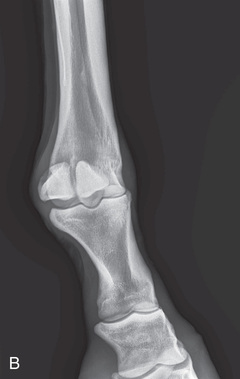

Digit/foot: P-III (distal phalanx, coffin bone) P-II (middle phalanx) P-I (proximal phalanx-pastern) Proximal interphalangeal joint (pastern joint) joint | DP (Standard) (Fig. 24.62B,C) | Dorsal 45-degree proximal–palmarodistal (D45Pr-PaDi) | Foot slightly forward on image receptor. | Perpendicular to foot axis at MSP (midsagittal plane) at area of interest with beam angled ~45 degrees to ground |

| Lateral (Standard) (Fig. 24.62D) | Lateromedial | On a block to elevate limb for P-III; resting on ground for other views. | 90 degrees lateral to MSP, parallel to ground on area of interest: coronary band for PIII | |

| Elbow joint | CdCr (Standard) | Caudoproximal-craniodistal- standing (CdPr-CrDi) | Weight-bearing with limbs evenly on ground and cassette against cranial aspect of joint at angle to the x-ray beam. | Caudal to joint; parallel to ground so beam perpendicular to radius. |

| Lateral (Standard) | Lateromedial standing (LM) | Weight-bearing with limbs evenly on ground; cassette against medial aspect of joint at angle to the x-ray beam. | 90 degrees lateral to MSP, parallel to ground on either the elbow joint or olecranon if required. | |

| Stifle | Caudocranial CdCr (Standard) | Caudoproximal-craniodistal standing (CdPr-CrDi) | Weight-bearing with limbs evenly on ground and vertical cassette against cranial aspect of patella at right angle to body wall, placed as far proximal and pushed as far medially as abdomen permits. | Caudal to the joint and directed downward to obtain a “tunnel” view of the distal femur. |

| Lateral (Standard) | Lateromedial | Weight-bearing with limbs evenly on ground and cassette against medial aspect of joint. | Laterally, parallel to the ground and centered distal and caudal to the patella. | |